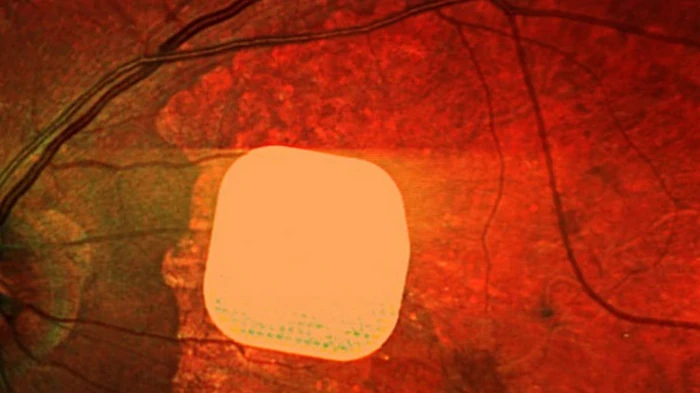

Британские врачи сделали значительный шаг в борьбе с возрастной слепотой. Об этом сообщает The Guardian. Офтальмологи из лондонской клиники Moorfields Eye Hospital вместе с коллегами из других европейских медицинских учреждений испытали ультратонкий электронный имплант Prima, который позволяет частично восстановить зрение пациентам с макулодистрофией - главной причиной потери зрения после 50 лет. Микрочип размером всего 2×2 миллиметра и толщиной с половину человеческого волоса хирургически устанавливают под сетчатку глаза. Во время операции, которая длится менее двух часов, пациенту также подключают систему очков дополненной реальности с камерой и миникомпьютером. Камера считывает окружающее изображение, преобразует его в инфракрасный сигнал и передает на микрочип, который активирует клетки сетчатки. Затем через зрительный нерв сигнал поступает в мозг, формируя визуальное восприятие. В исследовании приняли участие 38 пациентов с "сухой" формой возрастной макулодистрофии. До операции они полностью потеряли центральное зрение и могли видеть только периферийно. После имплантации и периода адаптации 84% участников снова смогли различать буквы, цифры и слова.